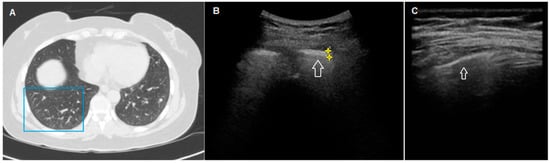

| Ultrasound findings, n (%) | |

| Thickness of the pleural line (>3 mm) | 43 (100%) |

| Irregular/fragmented/blurred pleural line | 42 (98%) |

| >3 B-lines | 38 (86%) |

| Subpleural nodes | 32 (74%) |